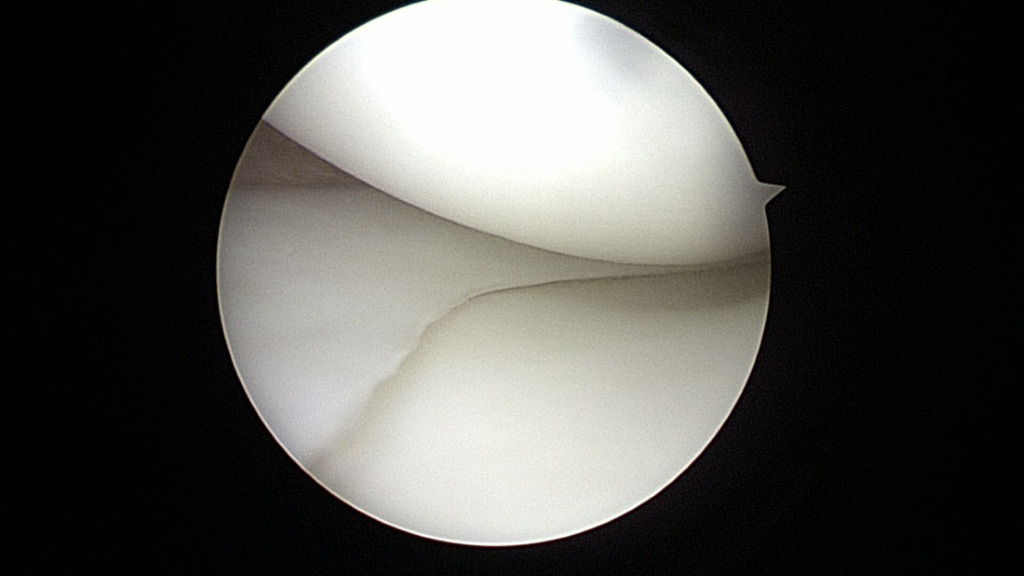

At the time of surgery, diagnostic arthroscopy revealed intact cartilage without any defects or abnormal wear. There was no evidence of a ligamentous injury. The medial meniscus was found to be intact (Figure 4).